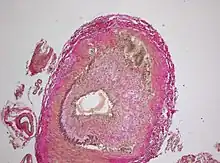

The gold standard for diagnosing temporal arteritis is biopsy, which involves removing a small part of the vessel under local anesthesia and examining it microscopically for giant cells infiltrating the tissue.[19] However, a negative result does not definitively rule out the diagnosis; since the blood vessels are involved in a patchy pattern, there may be unaffected areas on the vessel and the biopsy might have been taken from these parts. Unilateral biopsy of a 1.5–3 cm length is 85-90% sensitive (1 cm is the minimum).[20] A characterised as intimal hyperplasia and medial granulomatous inflammation with elastic lamina fragmentation with a CD 4+ predominant T cell infiltrate, currently biopsy is only considered confirmatory for the clinical diagnosis, or one of the diagnostic criteria.

- Histological features of temporal arteritis

- Intermediate magnification micrograph showing giant cell arteritis in a temporal artery biopsy. The arterial lumen is seen on the left. A giant cell is seen on the right at the interface between the thickened intima and media. H&E stain